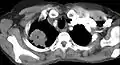

Tumor de Pancoast

Um tumor de Pancoast é um tumor do ápice pulmonar, ou seja, um tipo de câncer de pulmão definido principalmente pela sua localização situada no topo do pulmão esquerdo ou direito. É tipicamente associado a um histórico de tabagismo.